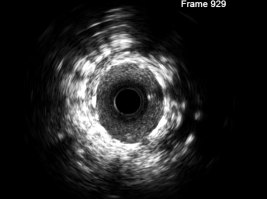

患者范先生,因“发作性胸痛5日”就诊于我院心内四科,入院后完善相关检查,诊断为冠状动脉粥样硬化性心脏病,不稳定型心绞痛。与患者沟通后,患者完善冠脉造影检查及血管内超声Ivus检查,提示前降支近中段斑块浸润,重度狭窄,导入Ivus后明确狭窄程度80%-90%,第二对角支开口部重度狭窄95%,给予球囊扩张及支架植入治疗。支架植入后,再次导入血管内超声Ivus,提示支架贴壁满意,无夹层及血栓征象。术后,患者胸痛症状改善,住院数日后,患者平安出院。